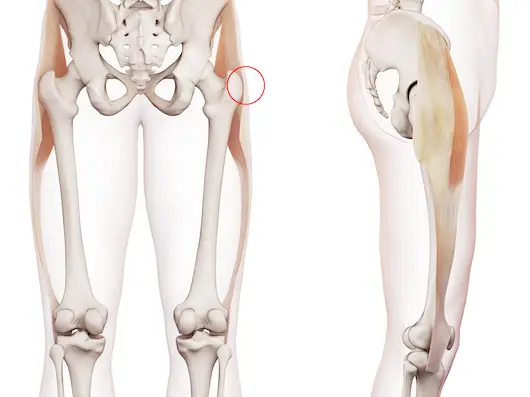

Priformis Sendromu Nedir?

Priformis sendromu (Piriformis Sendromu), kalça bölgesinde yer alan piriformis kasının siyatik sinir üzerine baskı yapması sonucu ortaya çıkan nöromüsküler bir rahatsızlıktır. Piriformis kası, kalça ekleminin derin kısmında yer alır ve uyluk kemiğini dışa döndürmeye yardımcı olur. Aynı zamanda yürürken, koşarken ve dengede dururken kalçanın sabitlenmesini sağlar. Normal koşullarda bu kas